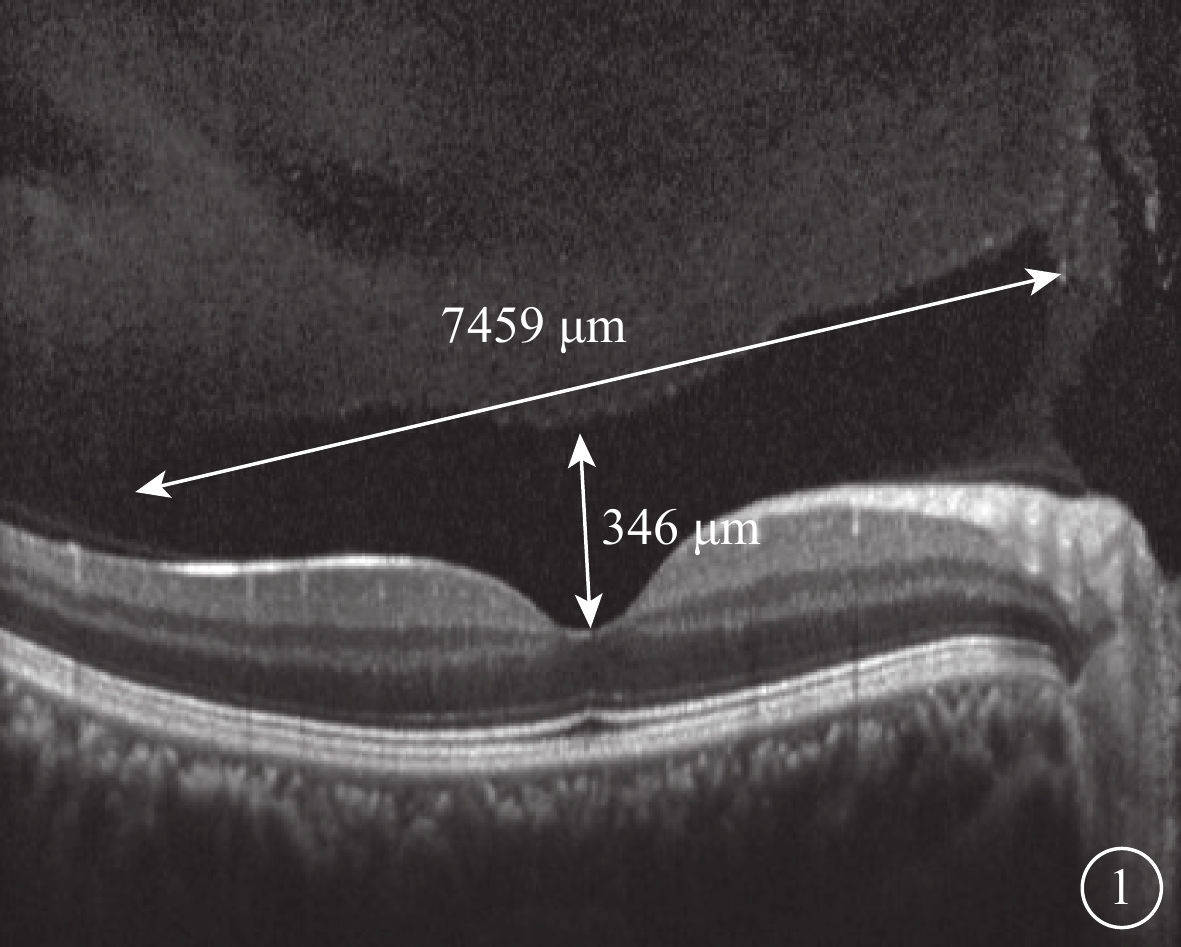

SD-OCT檢查,采用德國Heidelberg公司Spectralis OCT儀對黃斑和視盤進行橫向掃描,ART 60-100,波長870 nm,掃描寬度8.3 mm,掃描速度40 000次/s,掃描深度2.0 mm。檢查方法:(1)常規檢查,掃描焦點在視網膜。(2)后極部玻璃體掃描模式,掃描時視網膜圖像位于視窗偏下方,扭動掃描調焦旋鈕,使焦點稍往前移以加強后玻璃體成像,檢查黃斑區玻璃體的屈光補償約+2.00 D,視盤約+4.00 D。103只眼中,60只眼應用Heidelberg Eye Explorer軟件(version 1.9.10.0)手動測量圖像中結構完整的PPVP最大水平距離以及黃斑中心凹前垂直距離(圖1)。(3)全深度成像(FDI)掃描模式,在后極部玻璃體掃描模式基礎上,當圖像獲取到80%時立即啟動增強深部成像按鈕。103只眼中,采用FDI掃描模式檢查21只眼。

圖1

PPVP測量示意圖

圖1

PPVP測量示意圖

SD-OCT檢查,采用德國Heidelberg公司Spectralis OCT儀對黃斑和視盤進行橫向掃描,ART 60-100,波長870 nm,掃描寬度8.3 mm,掃描速度40 000次/s,掃描深度2.0 mm。檢查方法:(1)常規檢查,掃描焦點在視網膜。(2)后極部玻璃體掃描模式,掃描時視網膜圖像位于視窗偏下方,扭動掃描調焦旋鈕,使焦點稍往前移以加強后玻璃體成像,檢查黃斑區玻璃體的屈光補償約+2.00 D,視盤約+4.00 D。103只眼中,60只眼應用Heidelberg Eye Explorer軟件(version 1.9.10.0)手動測量圖像中結構完整的PPVP最大水平距離以及黃斑中心凹前垂直距離(圖1)。(3)全深度成像(FDI)掃描模式,在后極部玻璃體掃描模式基礎上,當圖像獲取到80%時立即啟動增強深部成像按鈕。103只眼中,采用FDI掃描模式檢查21只眼。

圖1

PPVP測量示意圖

圖1

PPVP測量示意圖